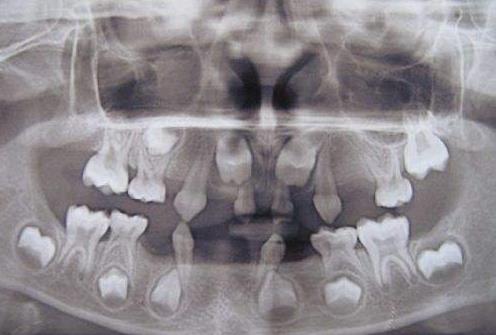

牙齒先天缺牙多顆

兒(er) 童無論是先天缺牙還是後天乳牙嚴(yan) 重齲壞,發現後都要及時做間隙保持器保留位置

再比如,拍片顯示下麵沒有恒牙牙胚,這種就說明是先天牙齒缺失,就建議在孩子小的時候及時發現及時做間隙保持器占位,等到孩子長大了再考慮修複。